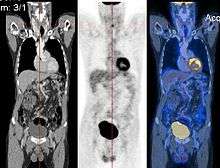

CT image (left), PET image (center) and overlay of both (right) after correct registration.

Image registration is a process that searches for the correct alignment of images.[9][10][11][12] In the simplest case, two images are aligned. Typically, one image is treated as the target image and the other is treated as a source image; the source image is transformed to match the target image. The optimization procedure updates the transformation of the source image based on a similarity value that evaluates the current quality of the alignment. This iterative procedure is repeated until a (local) optimum is found. An example is the registration of CT and PET images to combine structural and metabolic information (see figure).